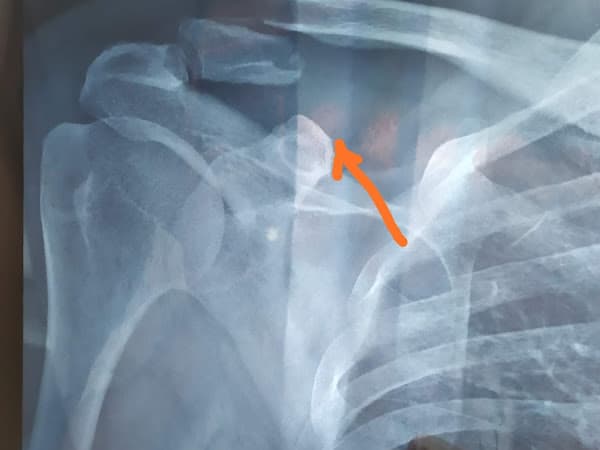

Tulang selangka kanan saya patah dan saya datang untuk menemui Dr. Ezam, dokter ortopedi. Beliau memberikan penjelasan menyeluruh tentang cedera saya dan juga apa yang diperlukan untuk memperbaikinya. Saya setuju untuk melanjutkan operasi, jadi saya dirawat di rumah sakit dan dipersiapkan. Saya mendapatkan peningkatan kamar gratis dan juga dirawat dengan sangat baik selama saya menginap. Operasi saya berjalan lancar dan pemulihan juga lancar. Perawat merawat saya dengan sangat baik dan sangat ramah. Dr. Ezam juga datang setiap hari untuk menemui saya hingga hari saya pulang. Saya pasti akan datang ke sini lagi untuk perawatan di masa mendatang dan juga sangat merekomendasikan rumah sakit ini kepada semua orang.